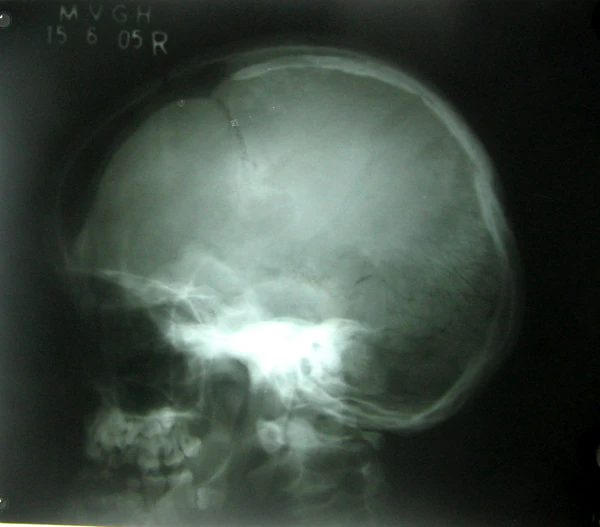

- Задержка закрытия (окостенения) пространства между костями черепа (родничков), могут формироваться дополнительные костные включения. Большой родничок может оставаться открытым в течение всей жизни.

- Брахицефалия.

- Высокий и выдающийся вперёд лоб.

Диагностика ключично-черепного дизостоза основана на клинических симптомах и рентгенологических исследованиях, которые включают изображения черепа, грудной клетки, таза и рук.